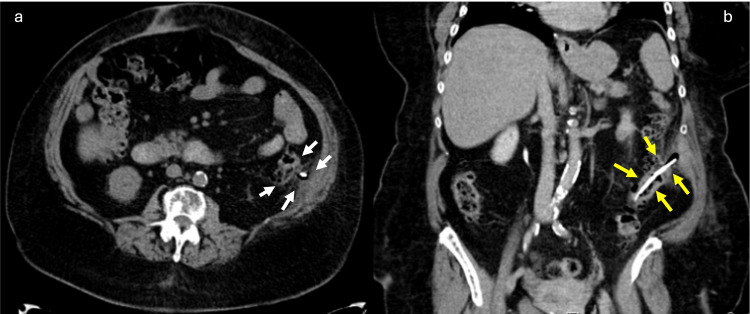

The clinical history and physical examination supported the presumptive diagnosis of acute pancreatitis (AP). Computed tomography for emergency assessment showed a tubular structure with hyper attenuation, located in the lumen of the sigmoid. The upper end of the stent transfixed the colon and peritoneal membrane, reaching the left abdominal wall with no signs of peritonitis (Figure 1).